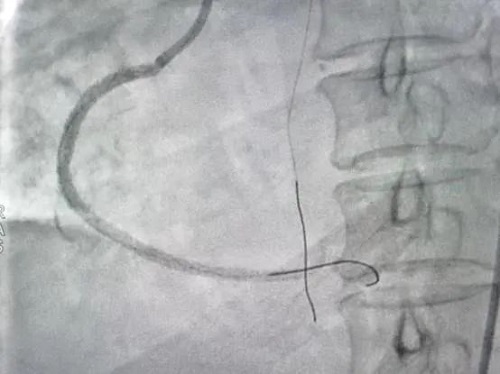

术中在前降支及高位钝缘支各植入支架1枚,正逆向尝试后开通右冠并植入支架3枚。

术后影像▼